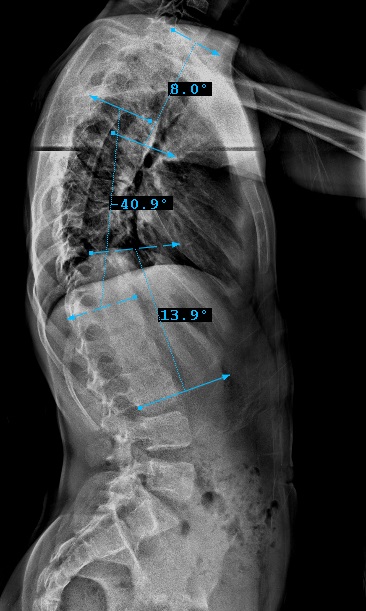

Preop: 1A+ Samples

Preop LEFT Bend